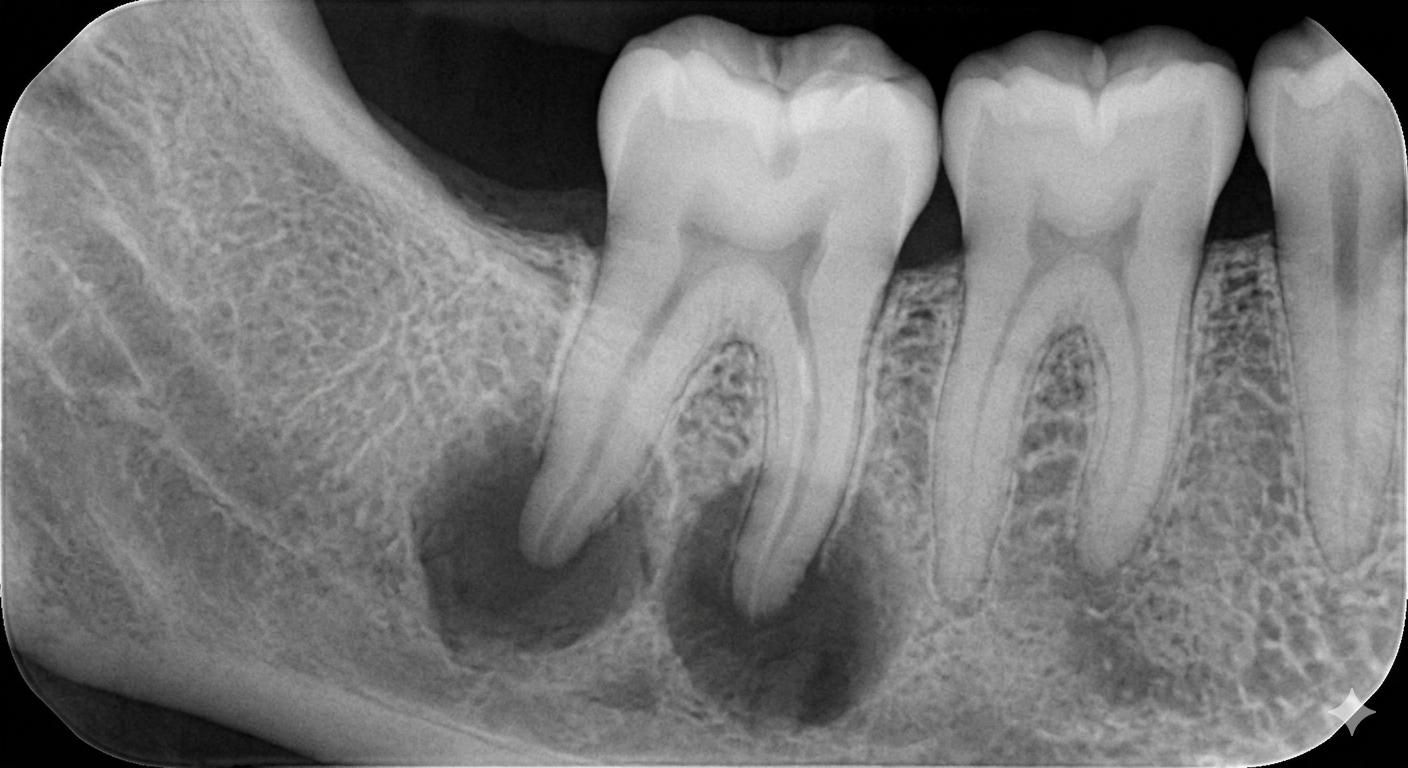

How a Dentist in Kasba Diagnoses the Need for a Root Canal

A professional diagnosis is essential.

Your dentist in Kasba may use:

- Clinical examination

- Dental X-rays

- Sensitivity tests

- Bite and pressure tests

Accurate diagnosis ensures the right treatment—no unnecessary procedures.